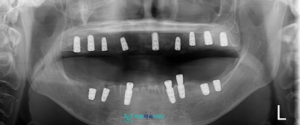

모든 준비를 마친 후,

의식하 진정요법을 적용하여

발치와 임플란트 식립을 같은 날

진행해드렸으며,

계획한 위치와 방향에 맞춰

임플란트가 잘 식립된 것을

확인할 수 있었습니다.